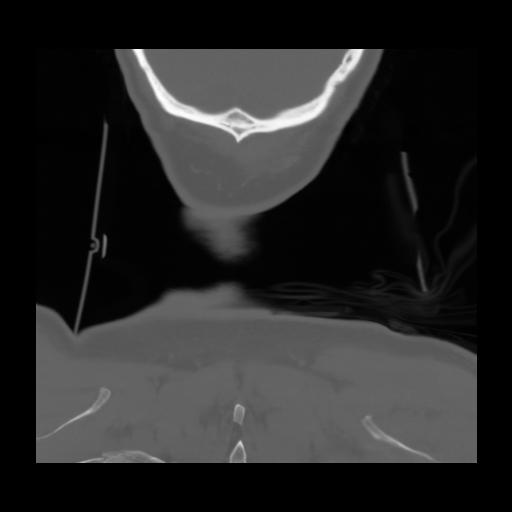

13 P.BLANDAS,,Coronal,2.000,P.BLANDAS,Coronal,